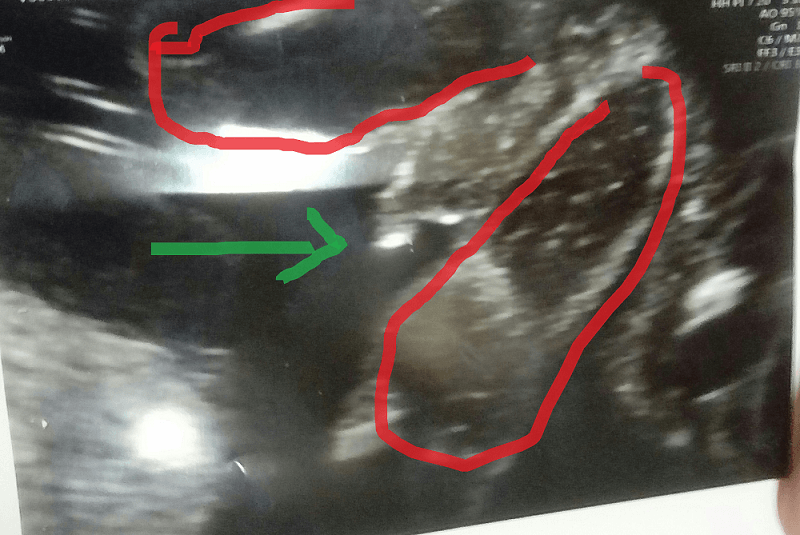

Strzałka przyrodzenie, czerwonym nogi oznaczyłam. Marta u Ciebie to i ja nawet widzę, ze chłopczyk... U mnie taka pewna nie jestem, ale to może przez to, że długo na dziewczynkę byłam nastawiona i moja psychika odrzuca myśl o chłopcu czy coś w tym stylu. Chociaż chłopiec też będzie cieszył, wiadomo. :)Zobacz załącznik 842408

Teraz jak to rozrysowałaś to faktycznie wygląda na chłopca bo na początku i ja nie wiedziałam co jest gdzie [emoji4] pewnie zostaje Ci czekanie do następnej wizyty, może pokaże się już konkretnie [emoji4]

No to teraz już wiem co gdzie jest :) Mnie to wygląda na siusiaka na 99%